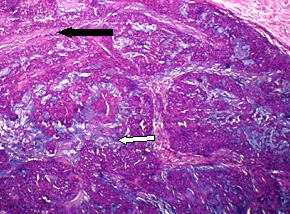

Histopathology examination showed a circumscribed neoplasm composed of sheets of round glomus cells collared around the blood vessels which were lined by normal endothelium [Table/Fig-2]. The intervening stroma showed myxoid change.

Histopathology examination showed a circumscribed neoplasm composed of sheets of round glomus (black arrows) cells collared around the blood vessels (bold white arrow) which were lined by normal endothelium. The intervening stroma (yellow arrow) showed myxoid change (Haematoxylin- Eosin stain, high power magnification)